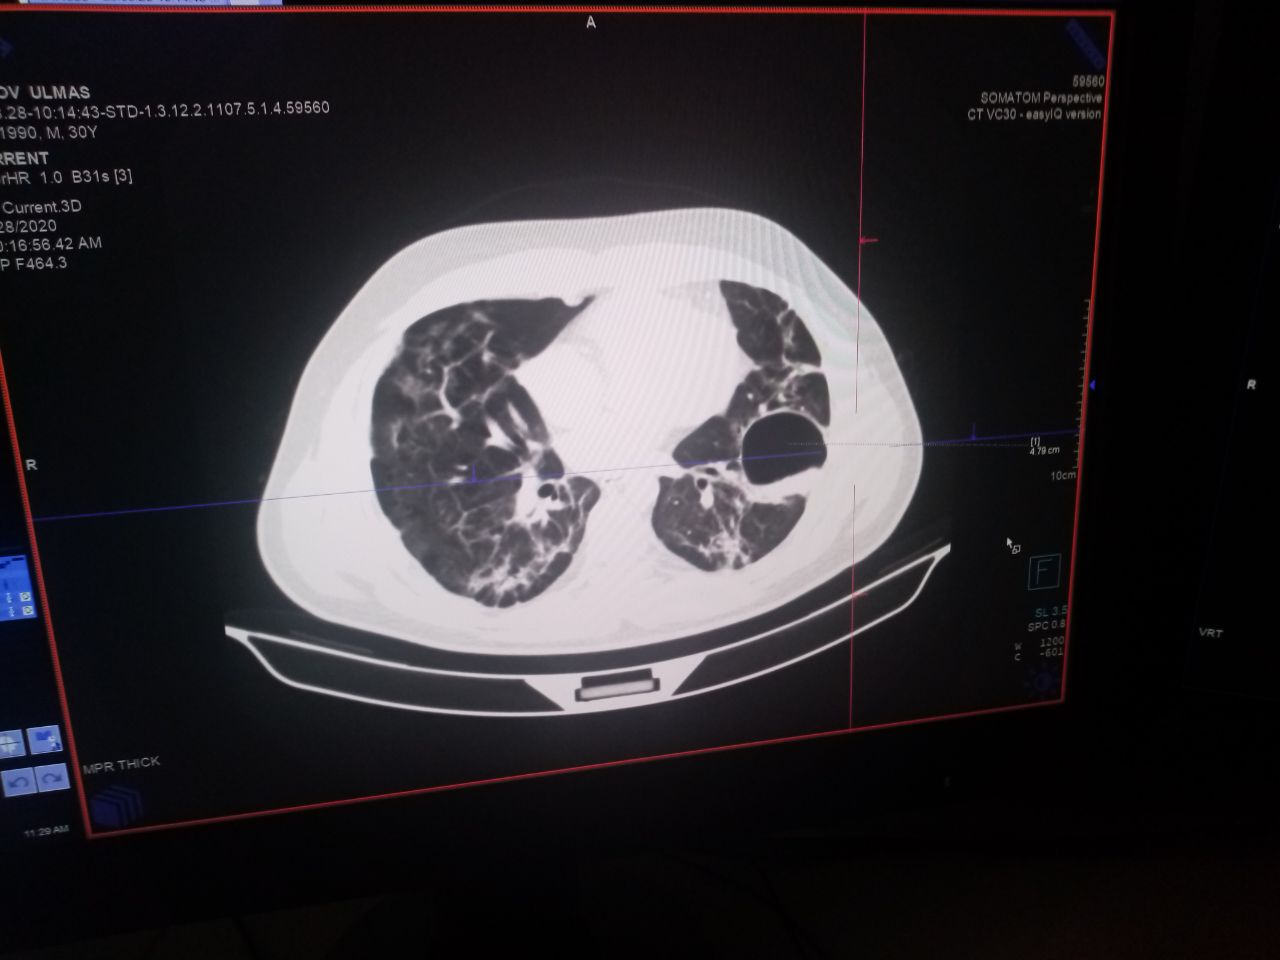

Здравствуйте посмотрите пожалуйста эту пленку

Это абсцесс?45 й день после ковид, одышка, молодой парень

30 лет, это туберкулёз ,с образов каверны?

Не понимаю это каверна или абсцесс после пневмонии вирусной этиологии?

Полость с уровнем

Надо смотреть соседние срезы и картинку вцелом

Качество распечатки и пленки не даёт этого сделать

Судя по наличию фиброза ковид был

Хорошо спасибо большое, у нас только такой снимок, диск не дают ,так как поток пациентов большой, это был ковид , но полость при ковиде ,странно

Либо была абсцедирующая тк жидкость в полости